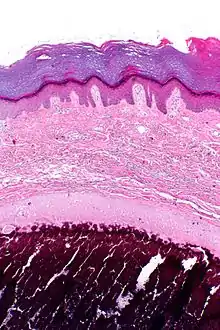

- Histopathology of calcinosis cutis in human tissue